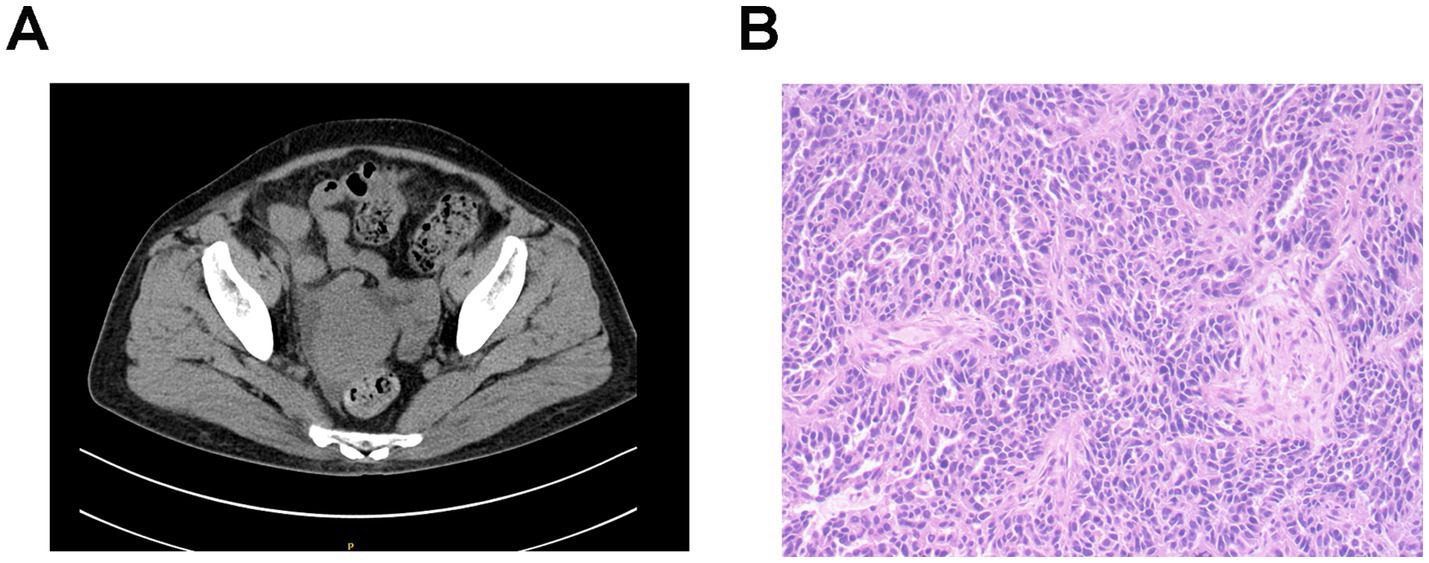

Gynecological ultrasound and abdominal CT scanning revealed a right adnexal cystic-solid mass (9.1 × 7.4 × 6.2 cm) and an irregular peri-uterine soft tissue lesion with poorly defined boundaries (5.3 × 6.0 cm), respectively. Tumor markers were significantly elevated (CA125 311.00 U/mL [normal<25], HE4 1414.00 pmol/L [normal<140]). The patient declined a renal biopsy and underwent cytoreductive surgery, which confirmed stage IIIC high-grade serous ovarian carcinoma (Figure 1). Post-operative management included intraperitoneal carboplatin and supportive therapy (metformin, insulin, statins, irbesartan, low molecular weight heparin, and diuretics). Tumor markers significantly declined post-operatively (CA125 191 U/mL, HE4 145 pmol/L), while proteinuria persisted (3+), and serum albumin decreased to 16 g/L but increased to 25.9 g/L after albumin infusions. Her renal function remained stable throughout hospitalization, and the patient was discharged with persistent edema.

Figure 1

Figure 1. Imaging and pathological characteristics of ovarian cancer in patient 1. (A) Abdominal CT scanning indicates an irregular soft tissue near the uterus without obvious boundaries with the uterus. (B) Histopathology shows right adnexal high-grade serous carcinoma. Tumor dimensions: 6.5 × 5 × 4 cm. Lymphovascular space invasion present (cancer emboli identified). Metastatic lesions identified in: right fallopian tube, right parietal peritoneum, and omentum. Uterus and left adnexa: carcinomatous involvement of the uterine serosal surface, and the left ovary and left fallopian tube show no significant lesions. Immunohistochemistry results: WT-1 (+), Vimentin (−), P16 + (patchy/mottled staining pattern), P53 (−), Ki-67 + (60% proliferation index), ER (−), PR (−), and PAX8 (+).